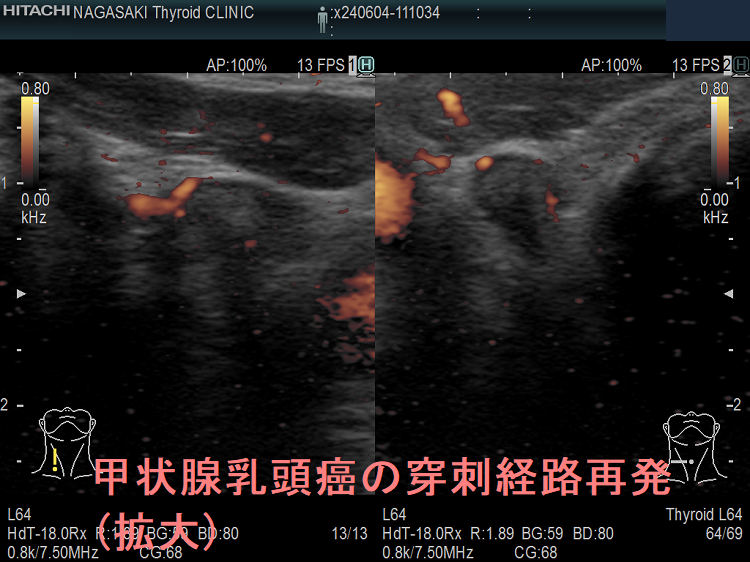

甲状腺乳頭癌の穿刺経路再発 超音波(エコー)画像

甲状腺乳頭癌の甲状腺穿刺細胞診後再発(穿刺経路再発) 超音波(エコー)画像

甲状腺乳頭癌の穿刺経路再発 超音波(エコー)画像 エラストグラフィー

甲状腺乳頭癌の甲状腺穿刺細胞診後再発(穿刺経路再発) 超音波(エコー)画像 エラストグラフィー青く見えます(硬い)

甲状腺乳頭癌の穿刺経路再発(拡大) 超音波(エコー)画像

甲状腺乳頭癌の甲状腺穿刺細胞診後再発(穿刺経路再発) 超音波(エコー)画像(拡大)

甲状腺乳頭癌の穿刺経路再発 超音波(エコー)画像(拡大) ドプラーモード

甲状腺乳頭癌の甲状腺穿刺細胞診後再発(穿刺経路再発) 超音波(エコー)画像(拡大) ドプラーモード